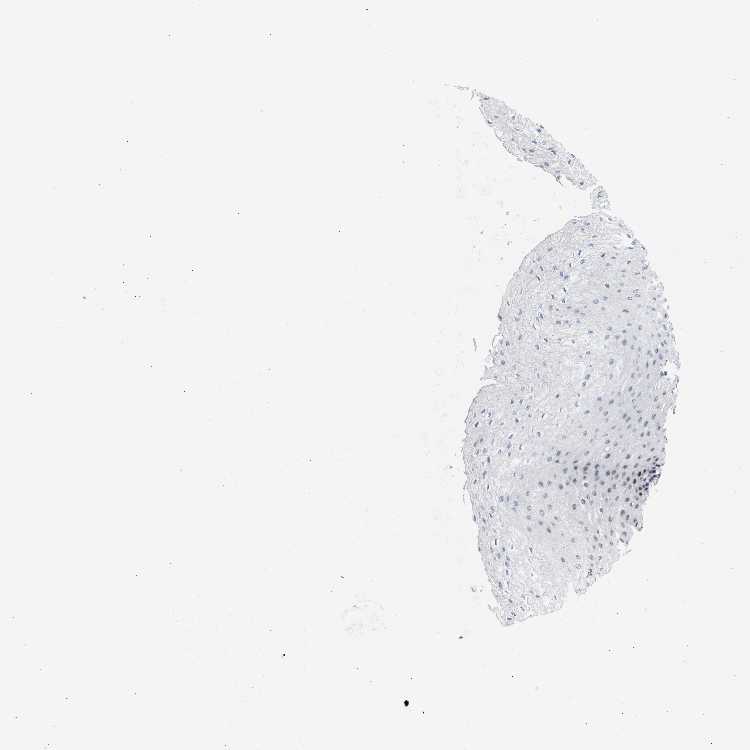

ESOPHAGUS - Antibody stainingi

Antibody staining in the annotated cell types in the current human tissue is reported as not detected, low, medium, or high, based on conventional immunohistochemistry profiling in selected tissues. This score is based on the combination of the staining intensity and fraction of stained cells.

Each image is clickable and will lead to virtual microscopy that enables deeper exploration of all samples and also displays staining intensity scores, fraction scores and subcellular localization as well as patient and tissue information for each sample.

Antibody CAB017635

Squamous epithelial cells Medium